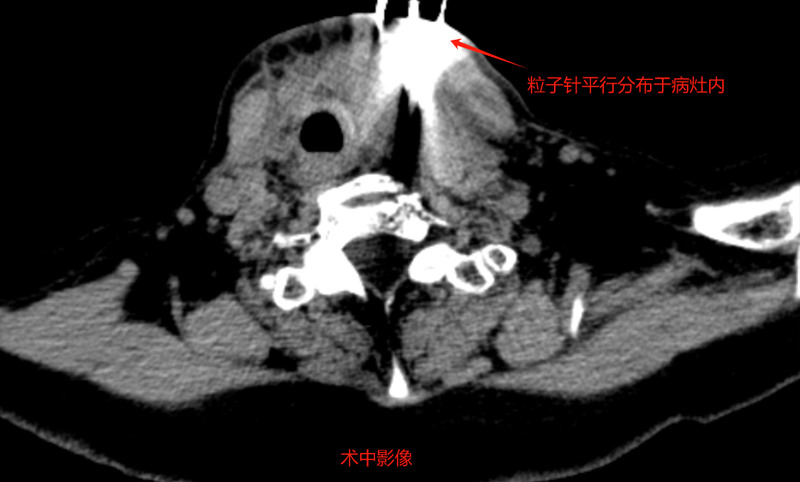

经过和患者家属的有效沟通,介入科团队为苑大娘补充了相关的检查,确定了治疗方案,于9月份在我院行“组织间粒子植入术”。由于复发病灶紧邻气管,且包绕了很多重要血管,无疑加大了操作难度。刘冰主任凭借多年的丰富经验,精细操作,将粒子精确植入到病灶内部,实现“精准爆破”。植入后患者无明显不适,很快顺利出院。